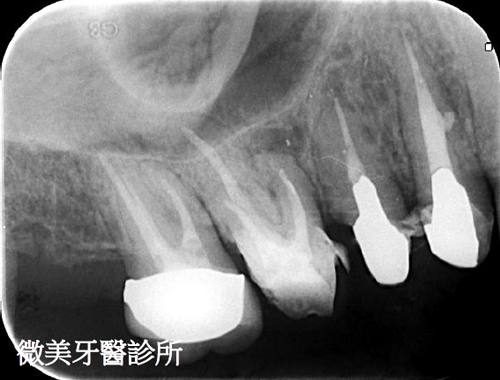

根管鈣化阻塞,利用顯微鏡搭配器械完成多根管治療

原先根管治療未完整,利用顯微鏡重新根管治療,達到多根管封填